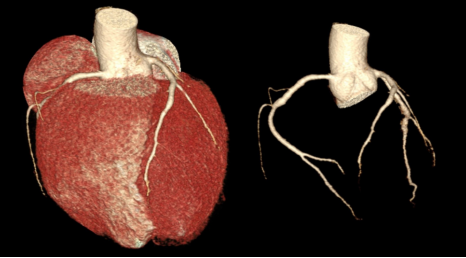

心脏及冠脉VR重建  显示心脏及冠脉的三维立体形态

冠脉CTA可以很好地观察冠状动脉是否有硬化、钙化、斑块情况以及管腔是否狭窄、闭塞,也可以评估冠状动脉支架或搭桥术后血管情况,在临床上准确率可以高达90%以上。